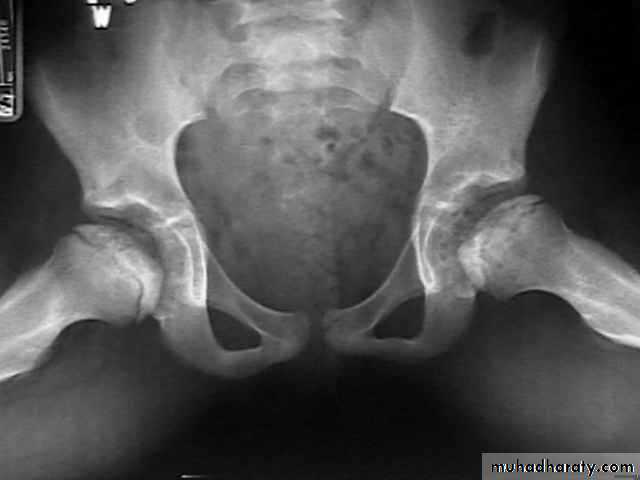

DEVELOPMENTAL DYSFLASIA OF HIP (CONGENITAL DISLOCATION OF THE HIP)

• An abnormally lax joint capsule allows the femoral head to fall out of the acetabulum, leading to deformation.• Predisposing factors for the development of CDH are:

• * Abnormal ligamentous laxity (effect of estrogen; fema1e:male = 6:l)

• * Acetabular dysplasia .

• CDH occurs most commonly (70%) in the left hip. Bilateral involvement is seen in 5%.

• Radiographic features

• US (commonly used today) at 1-3 months

• * Normal femoral head is covered at least 50% by acetabulum , In CDH < 50% of femoral head is covered by acetabulum .

Plain film

At 3-6 months :By doing special veiw (Von Rosen veiw )by abduction of the thigh 45 degree and internal rotation .

In DDH the lines that drown through the femura will meet in higher level than the normally should at lumbosacral joint .

6 months and later

* AP veiw ( femural epiphysis are visualized ):* Superolateral displacement of proximal femur (disturbed shenton’s line )

* Increase in acetabular angle

* Small capital femoral epiphysis

Femoral head is located lateral to Perkin's line

* Other features that are sometimes present

Abnormal sclerosis of the acetabulum

Shallow acetabulum

Formation of a false acetabulurn

Delayed ossification of femoral head